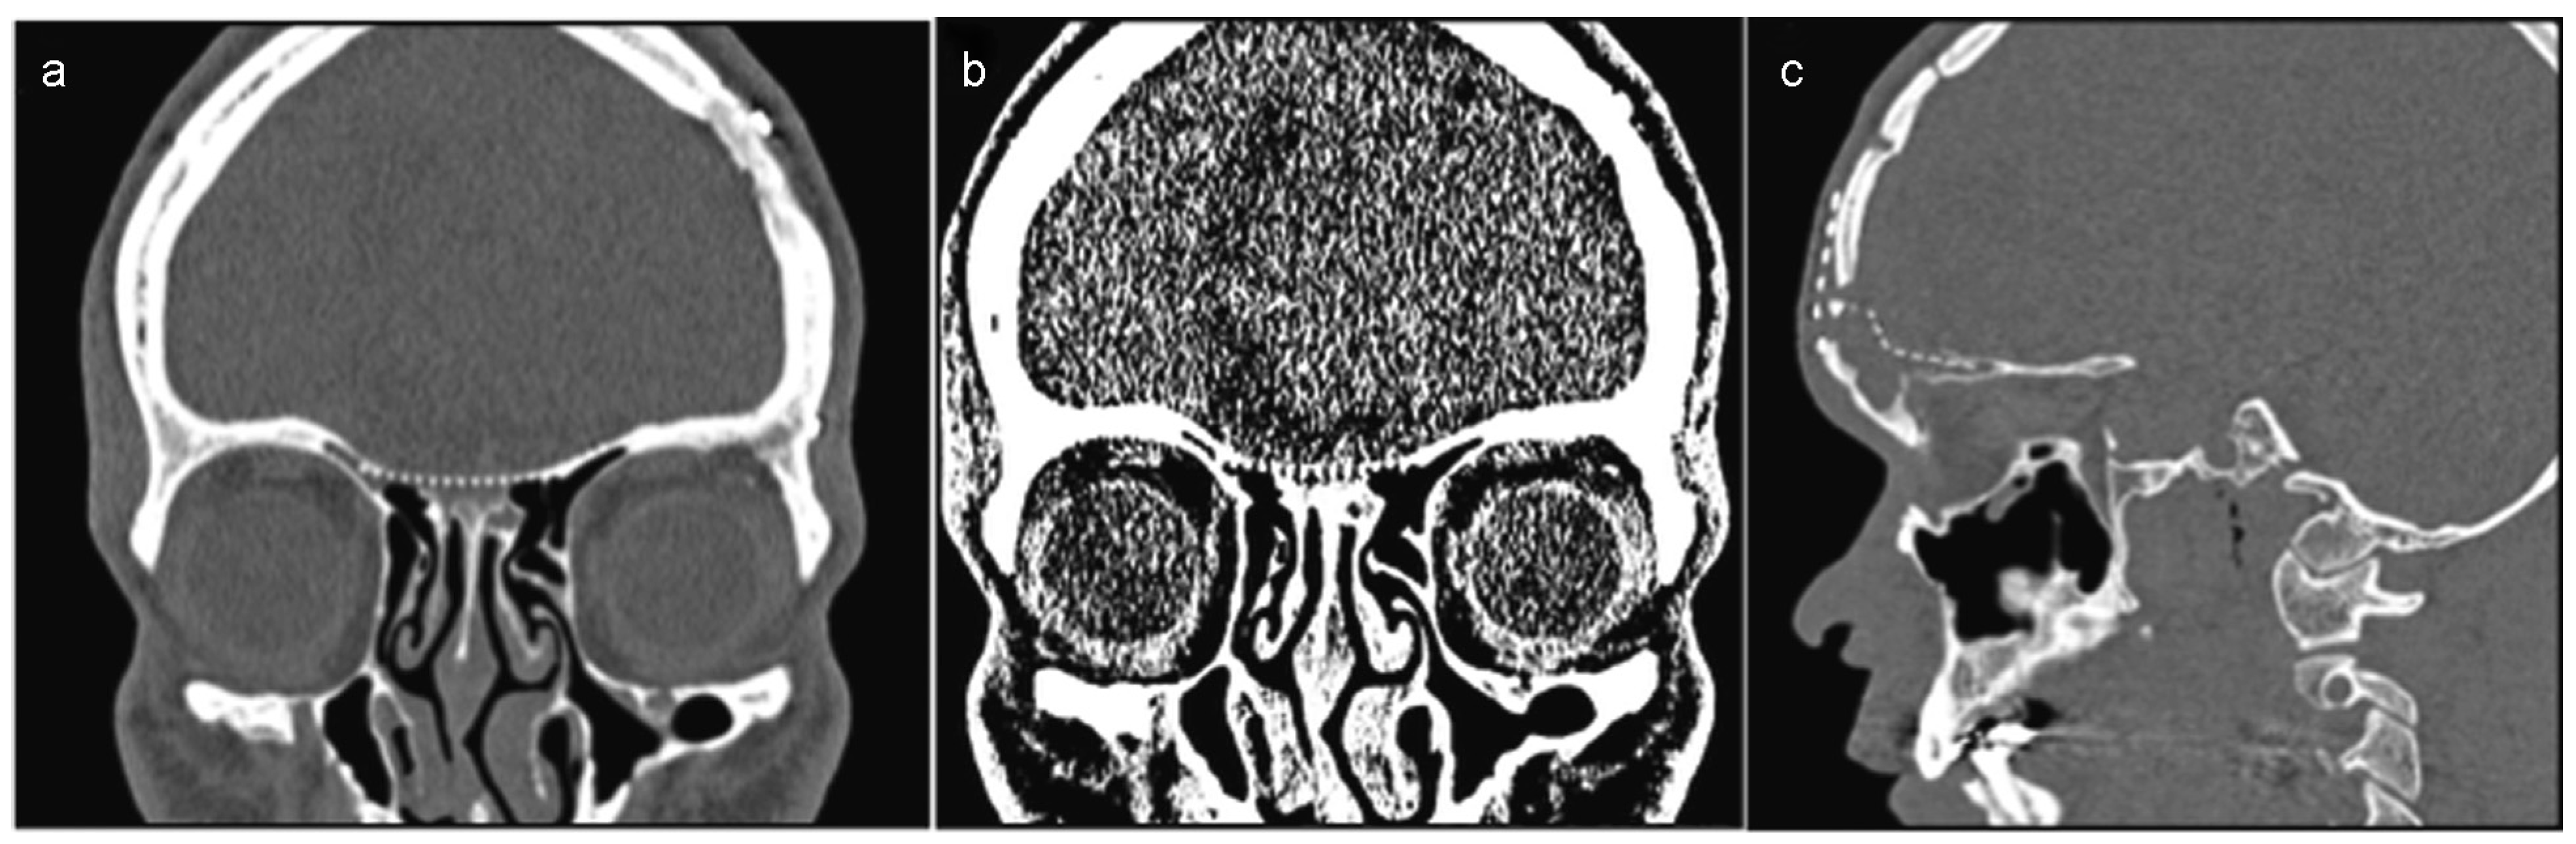

Figure 9. (a–c) Postoperative result of CT scan shows separation of the brain from the nasal cavity with the help of the mesh.

Following this second operation, the patient remained in the hospital receiving antibiotics (cefuroxime and clindamycin) for 5 days and a postoperative CT revealed that with support from the titanium mesh, the anterior skull base had been successfully reconstructed (Figure 9a–c). The patient was discharged on the sixth day and exhibited good postoperative recovery, with no episodes of pulsatile headache, dizziness, and nausea (Figure 10). A 12-month postoperative CT did not demonstrate any alterations (Figure 11a–c).